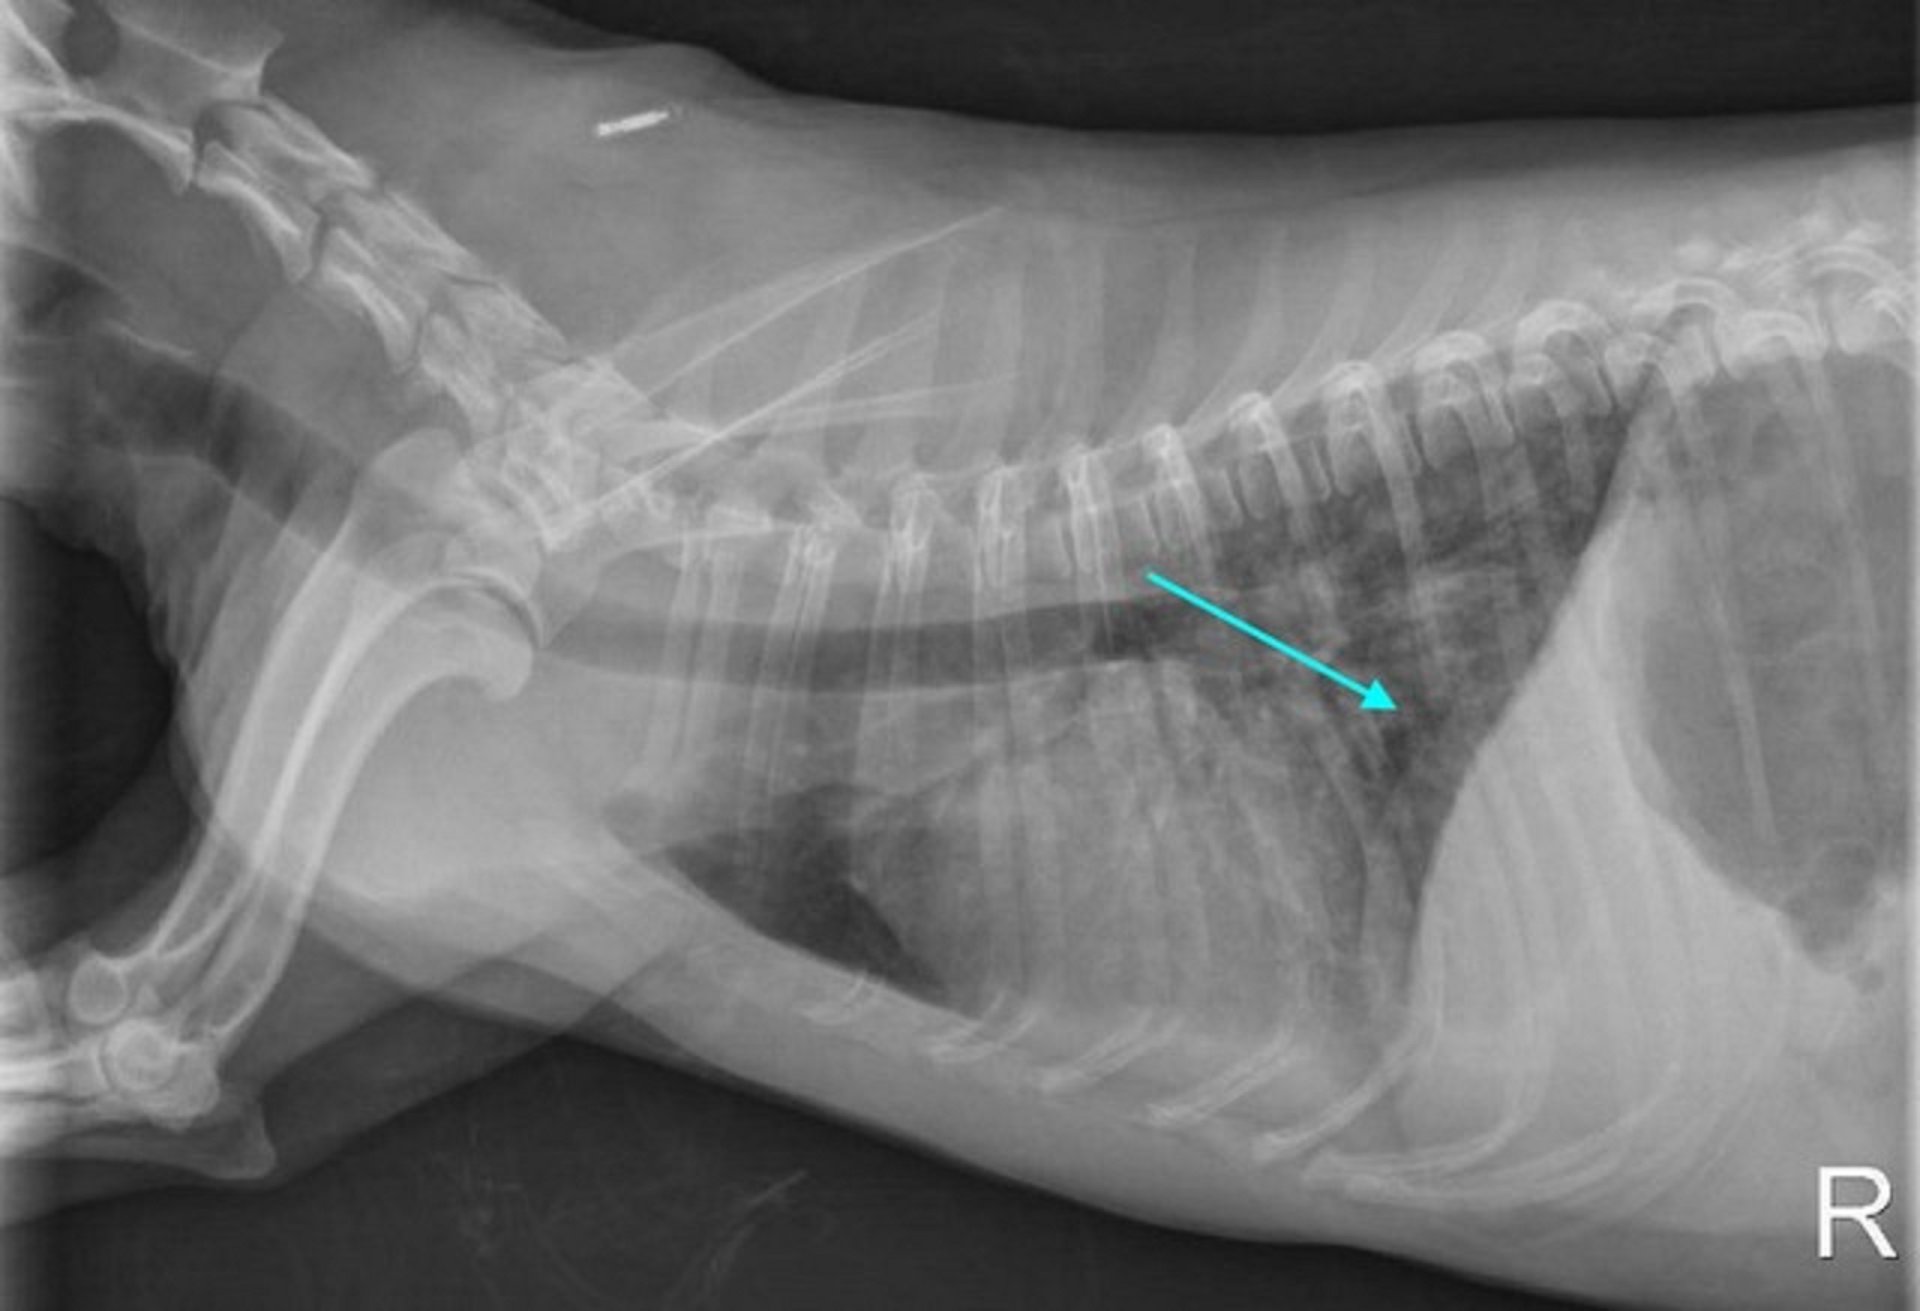

胸部 X 线片可能显示弥漫性或尾背网状结节性肺混浊,可能是由于肺出血。 腹部 X 线片可能正常,也可能显示肾肿大或肝肿大。

由 Katharine F. Lunn 博士友情提供。